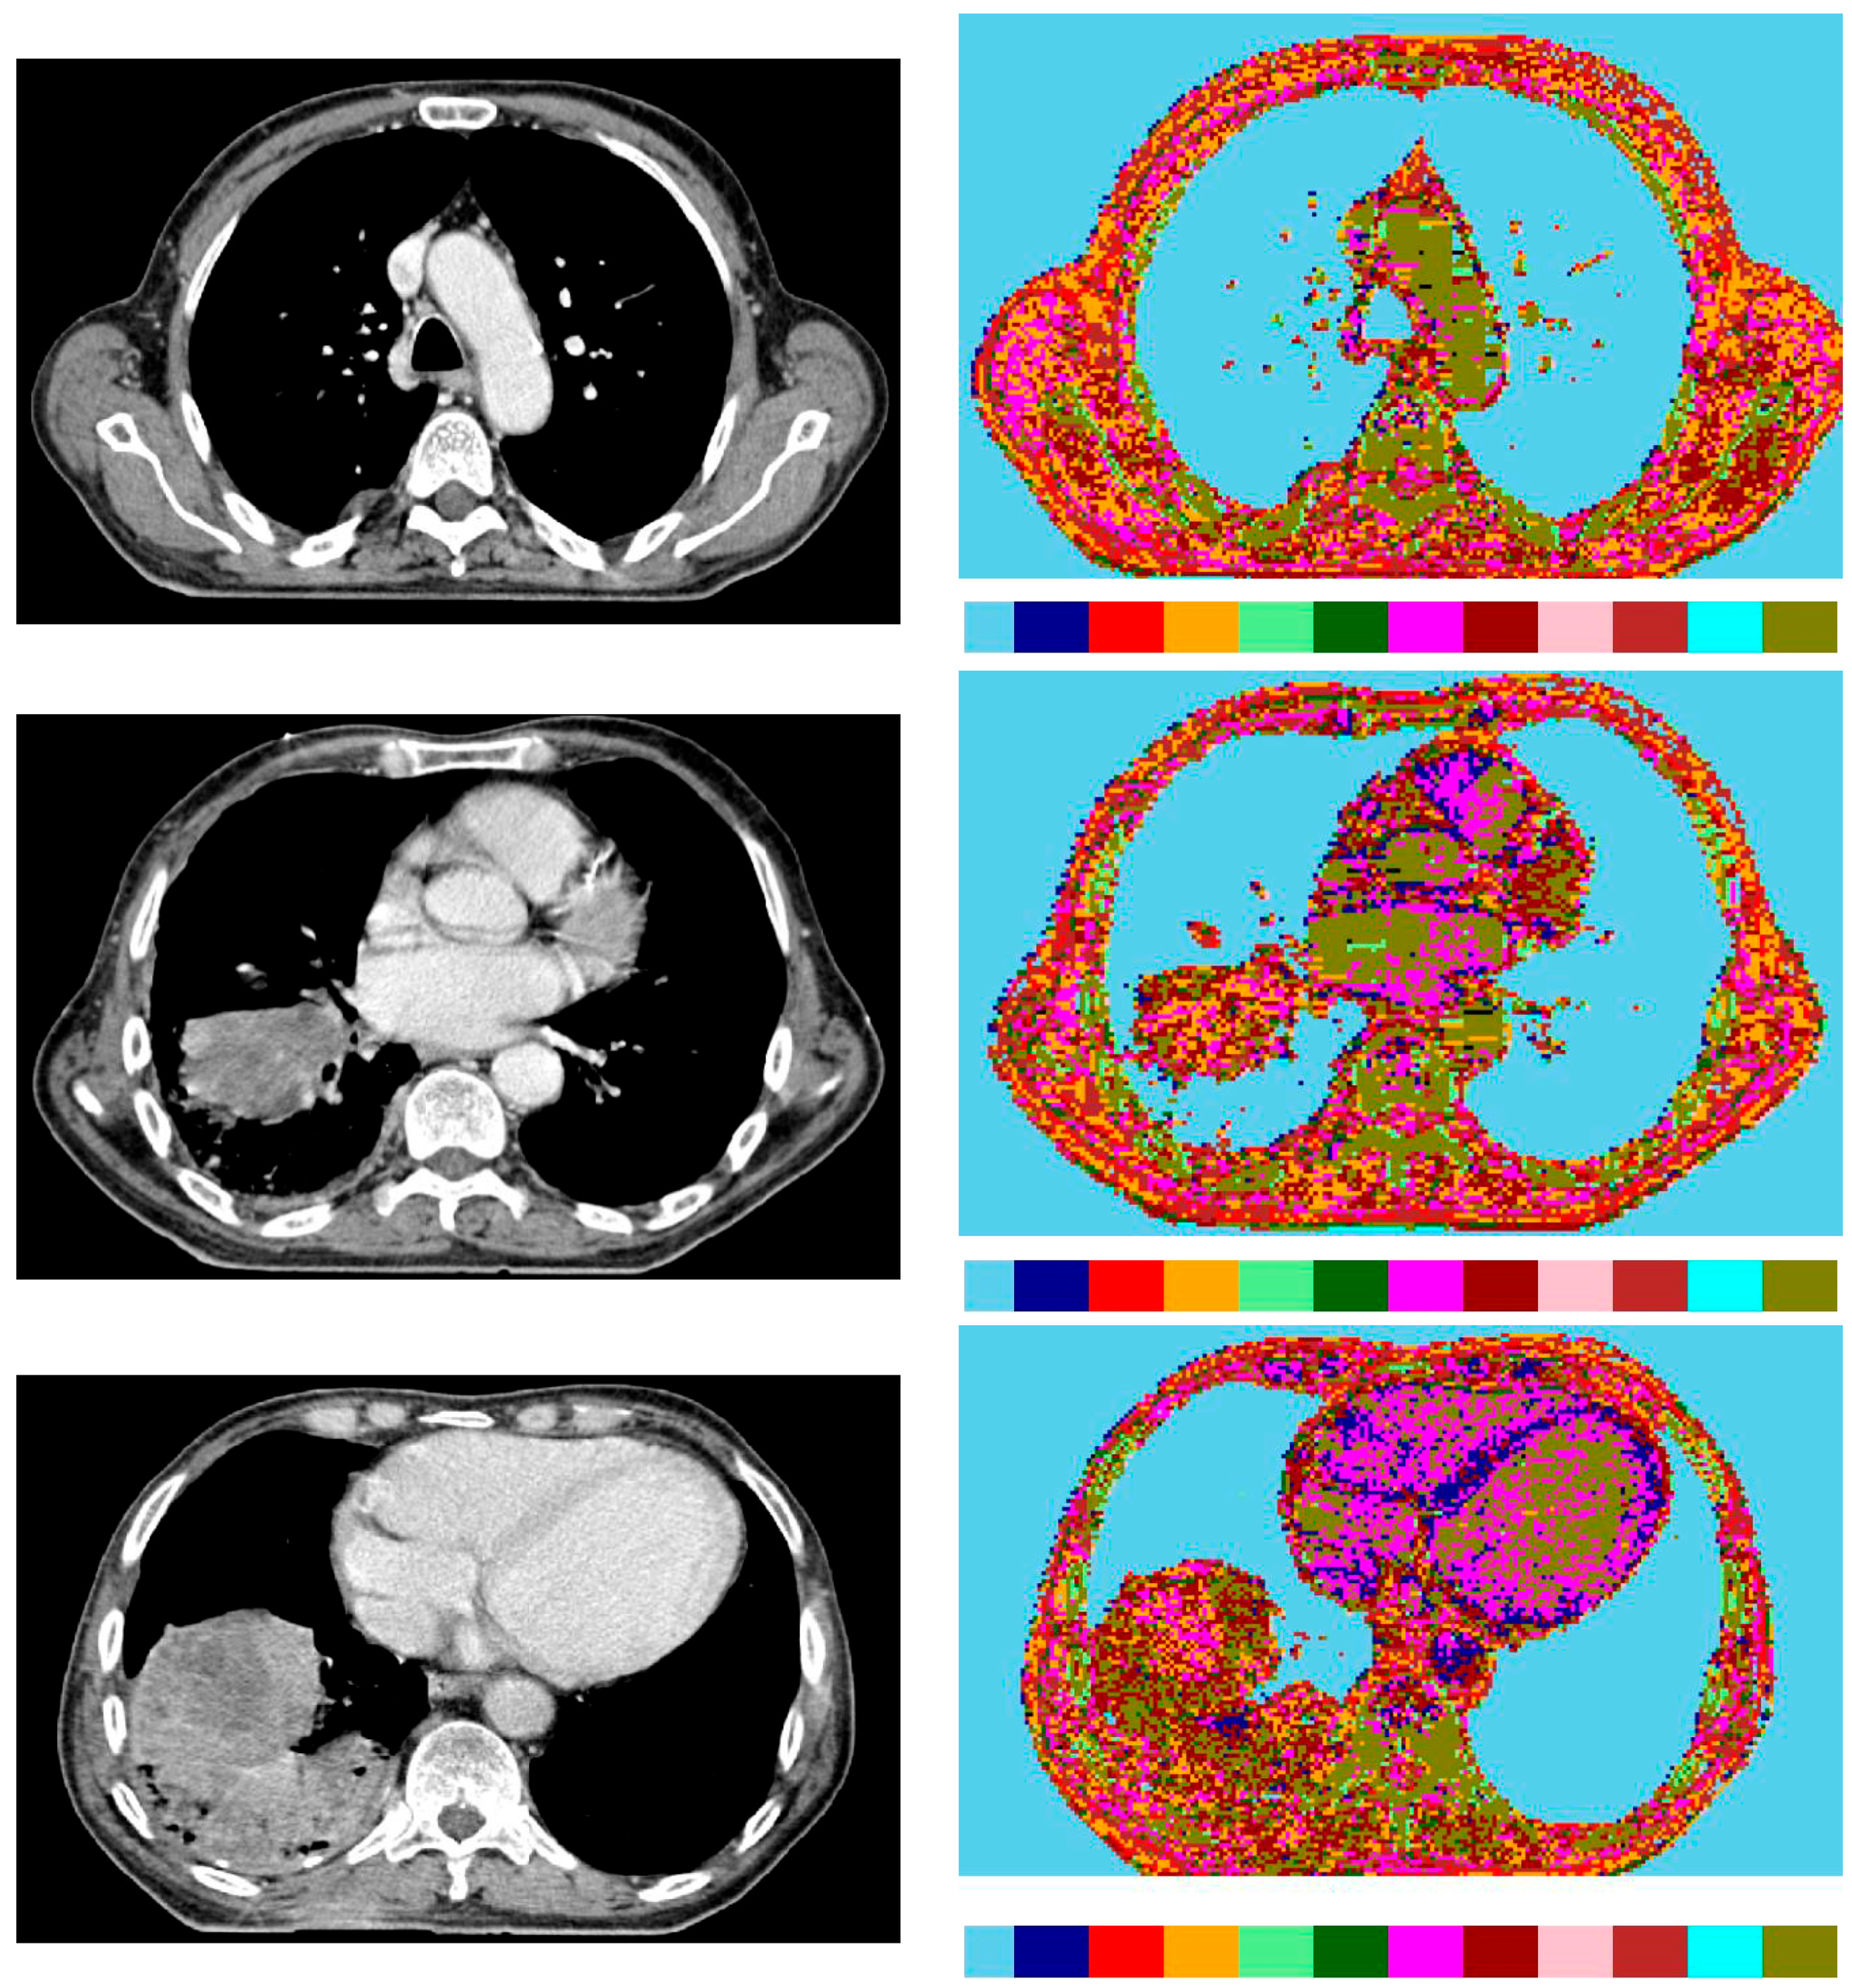

- The second dataset of images is from the patients with lung tumours; there are 11,210 CT images and 25 pathology slices collected from 6 patients. From these, we selected 10 images from 2 patients with lung adenocarcinoma. Usually, lung adenocarcinomas show an admixture of many architectural patterns such as acinar, papillary, micropapillary, lepidic, and solid growth patterns [32,33].

- The third dataset of images is extracted from a collection of 52,072 images from 422 patients with non-small cell lung cancer (NSCLC) [34]. For these patients, pre-treatment CT scans lung tumours; manual delineation by a radiation oncologist of the 3D volume of the gross tumour volume and clinical outcome data are available in [31] for the Lung1 dataset. Typically, lung cancer pathology can identify two groups of cancer cells: small cell lung cancer (SCLC) and non-small cell lung cancer (NSCLC). Then, the last ones, the NSCLC, are divided again into squamous cell cancer (SCC), large cell cancer, and lung adenocarcinoma. Finally, in situ (ISA) and invasive are the two types of lung adenocarcinoma.

3.1.2. Medical Images

| Non-small cell lung cancer | Computer tomography (CT) scan | 1/1 | avg. 1802 × 884 | 1372 × 672 | 4 × 4 | 57,624 |